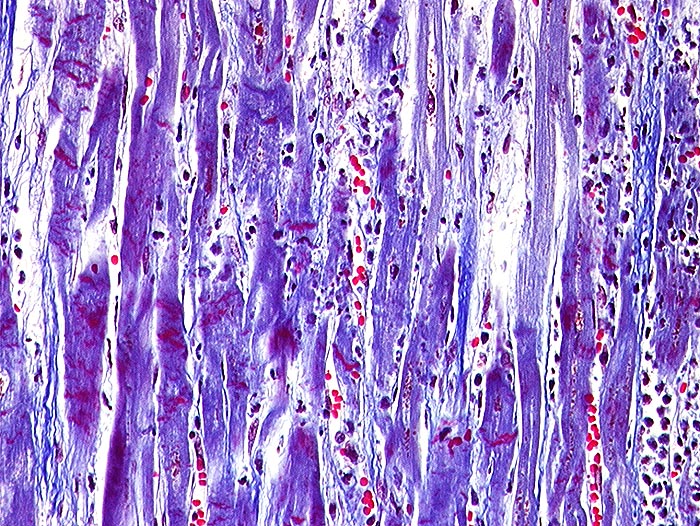

Akuter Myokardinfarkt: Kontraktionsbänder

Quer zu den Myozyten verlaufende rot gefärbte Kontraktionsbänder. Granulozytäres Infiltrat rechts im Bild.

Paninfarkt bei schwer stenosierender Koronarsklerose mit Abgangstenose beider Hauptäste. Alter Verschluss der Arteria coronaria dextra.

Kontraktionsbänder sind nach 30 Minuten, zelluläre Infiltrate nach minimal 3 Stunden sichtbar. Kontraktionsbänder entstehen, wenn das hypoxisch geschädigte Myokard sich noch kontrahiert, aber nicht mehr relaxieren kann.